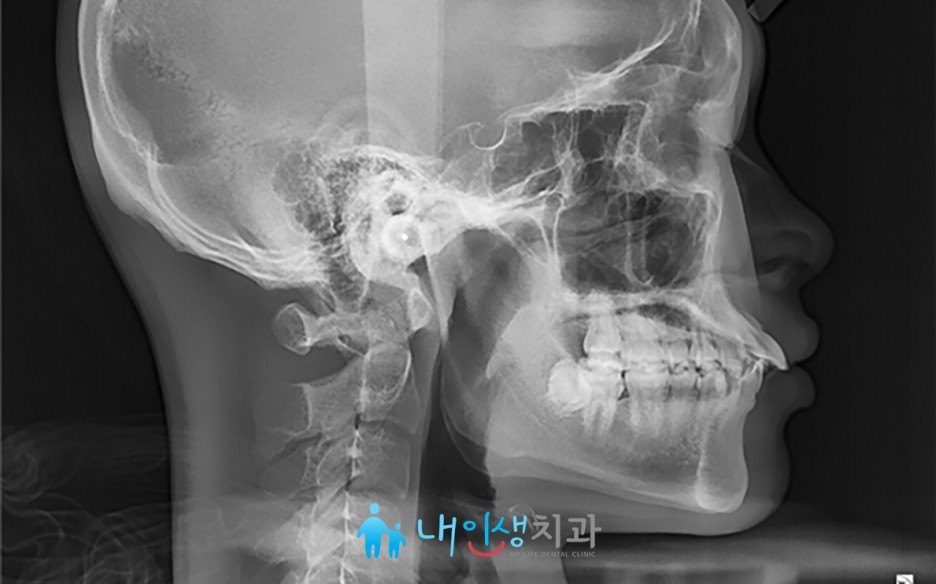

상악동 누공 폐쇄 케이스

안녕하세요. 내인생치과 신창훈입니다. 이번에 소개해 드릴 환자분은 발치후 상악동이 천공 되어서 입안의 물이 코로 들어가고 코로 바람이 새는 증상이 있어서 발치한 치과에서 비흡수성 차폐막으로 막은 상태로 오셨습니다. 저희 치과에 오신 거는 발치한 날로부터 약 3주가 지난 상태로 오셨는데 발치한 치과에서는 한달이 안 되었기 때문에 더 기다려 볼 것을 권유 받…